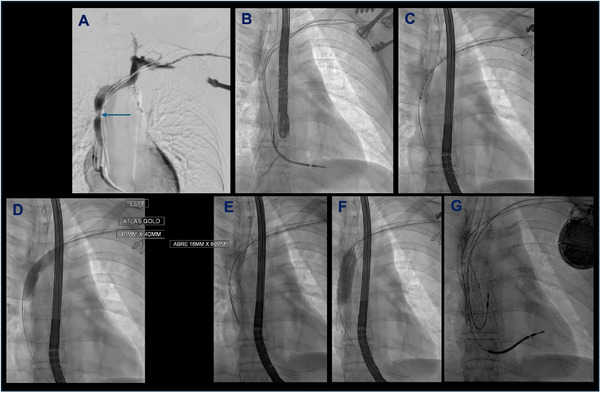

Background and aims: Central venous obstruction (CVO) increases the complexity of pacing interventions, whether it be with device-associated symptomatic superior vena cava syndrome (SVCS), or by impeding new implants. Endovascular treatment involves the joint expertise of both cardiac pacing and vascular specialists. We report the outcomes of such procedures at our institution.

Methods: A single-center retrospective observational study, examining outcomes of joint pacing-vascular procedures for CVO. Cases were screened from an existing institutional database.

Results: There were 19 total cases. Two were new device implants where the novel "inside-out" procedure was utilized to establish access in SVCS, both with no complications. The remainder (n = 17) were transvenous lead extractions plus attempted recanalization of CVO using venoplasty with or without stenting. Transvenous devices were re-implanted in eight patients. Complete procedure success rate was 84%. There were two cases of pericardial effusion requiring pericardiocentesis, resulting in procedure abandonment. There was no in-hospital mortality and no cases of emergency sternotomy. Over mean follow-up of 28 months, 2/6 patients receiving venoplasty (33%) and 2/8 patients receiving stenting (25%) required re-intervention for symptomatic restenosis. Of the patients who were not re-implanted with a transvenous device following initially successful endovascular intervention (6/14), none had recurrence over the follow-up period.

Conclusion: Pacing interventions in SVCS carry a significant risk profile, requiring management by experienced operators in high-volume centers to maximize safety. Endovascular interventions have a significant recurrence rate, with up-front stenting potentially being superior. Our data suggests that those without re-implantation of transvenous leads may have better long term outcomes.